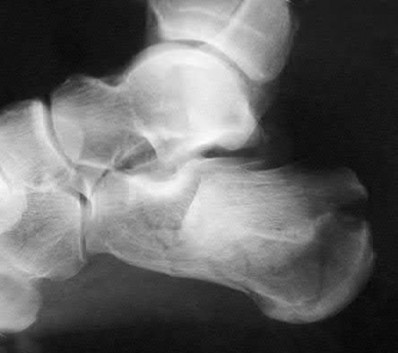

A 25-year-old female is involved in a motor vehicle collision. She presents with the isolated injury seen in Figures A through D. Her leg is swollen but her skin is intact. She has no clinical signs of compartment syndrome. Which of the following treatment options will allow for maintenance of fracture alignment and minimize the risk of soft tissue complications?

The patient presents with a closed distal third metaphyseal-diaphyseal distal tibia fracture with simple intra-articular extension. Immediate intramedullary nailing along with percutaneous fixation of the articular component provides appropriate restoration of length, rotation and alignment and minimizes the risk of wound complication.

Displaced distal third tibia fractures may be associated with simple intraarticular extension. Operative treatment of intra-articular distal tibia fractures has historically been performed with open reduction and internal fixation. Early open reduction and plate fixation of pilon fractures has been associated with high rates of infection and wound complication. In select patterns with simple articular extension, percutaneous screw fixation and medullary nailing may provide appropriate reduction with minimal soft-tissue risk.

Figures A and B demonstrate a distal third tibial shaft fracture with simple intra-articular extension. The axial and coronal CT cuts in Figures C and D further clarify the articular injury. Illustrations A and B demonstrate a comminuted distal third tibial fracture with simple intra-articular extension. Illustrations C and D are fluoroscopic images of the same injury after intramedullary nailing and percutaneous fixation of the articular component.